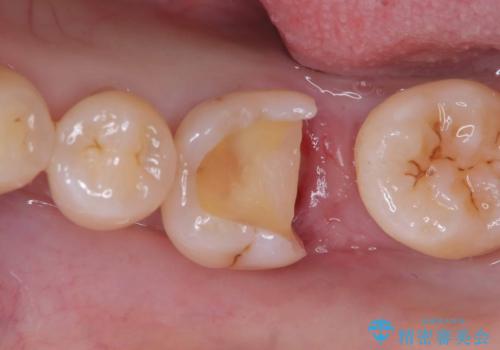

実際の治療ではVPTを施行し、その後痛みなどの症状もなく経過は良好でしたので、最終的にセラミックインレーによる修復を行いました。

生活歯髄療法(VPT)とは、本来であれば虫歯除去中に神経(歯髄)が露出した場合、すべての神経を取り除く「抜髄処置」が必要になります。しかし、術前の検査結果や、顕微鏡下で確認した神経の状態・出血の様子などをもとに判断し、バイオセラミックという生体親和性の高い材料を使用して、汚染された部分の神経のみを除去し、健康な神経は残すことができる治療法です。

この治療によって、神経を保存しながらも、神経のある歯と変わらない機能を保つことが可能になります。

また、長期的に神経を保存していくためには、適合性が高く、経年劣化しにくい材料を使用することが重要です。今回はそうした観点から、セラミックインレーで最終的な修復を行いました。